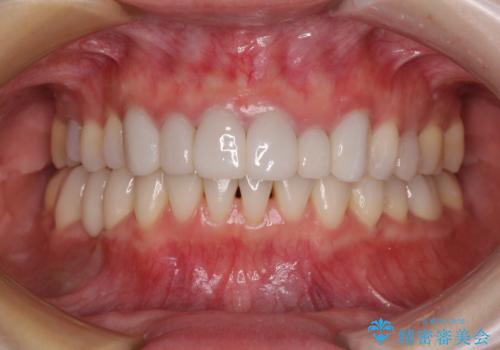

- 失活により変色した歯と不揃いな口元を気にして来院された患者様です。

口元をインビザラインにより歯列を整え、その後に失活している奥歯をオールセラミッククラウンにて補綴治療することとしました。

長時間のマウスピース装着と、患者様自身でのゴムかけに協力いただき、自然な口元に仕上げることができました。

気になっていた変色した歯もオールセラミッククラウンで本物の歯のようになり、患者様には大変満足していただきました。